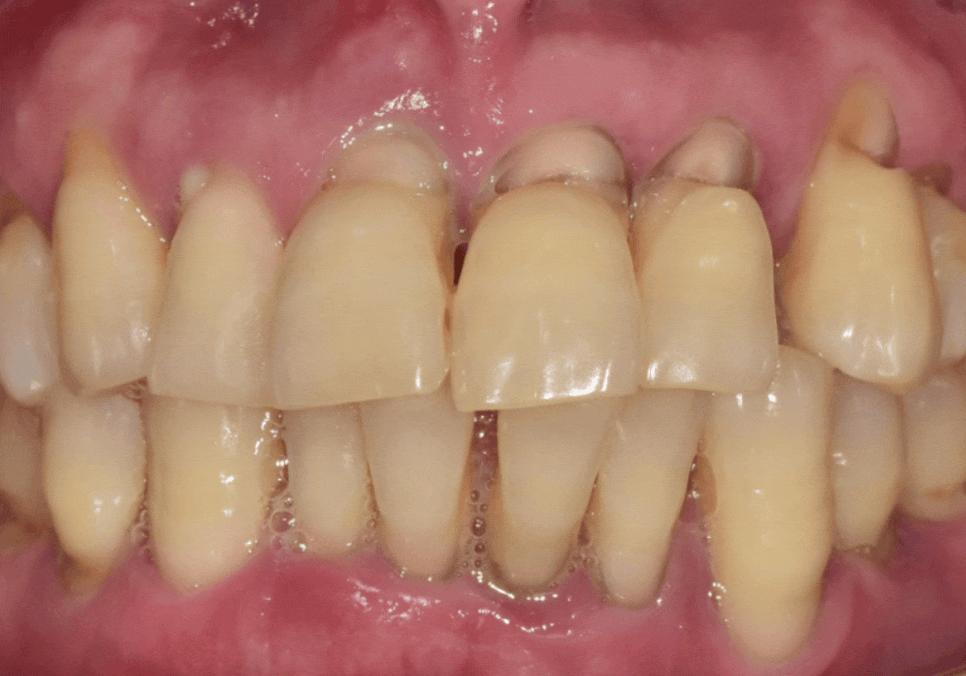

얼마 전 저희 치과를 찾으신

고령 환자분의 사례를 소개해 드릴게요.

이 환자분은 치아 뿌리 쪽이

아주 깊게 패어 있는 모습인데요.

오랜 세월 동안 마모가 서서히 진행되어,

육안으로 봐도 치아 안쪽의 신경이

드러날 정도로 심각한 상태였습니다.

보통 이 정도로 패여서 신경이 노출되면

물만 닿아도 자지러지게 아픈 게 정상이에요.

그래서 대부분은 신경치료를 하고

치아를 씌워주는 크라운 치료를 진행하게 됩니다.